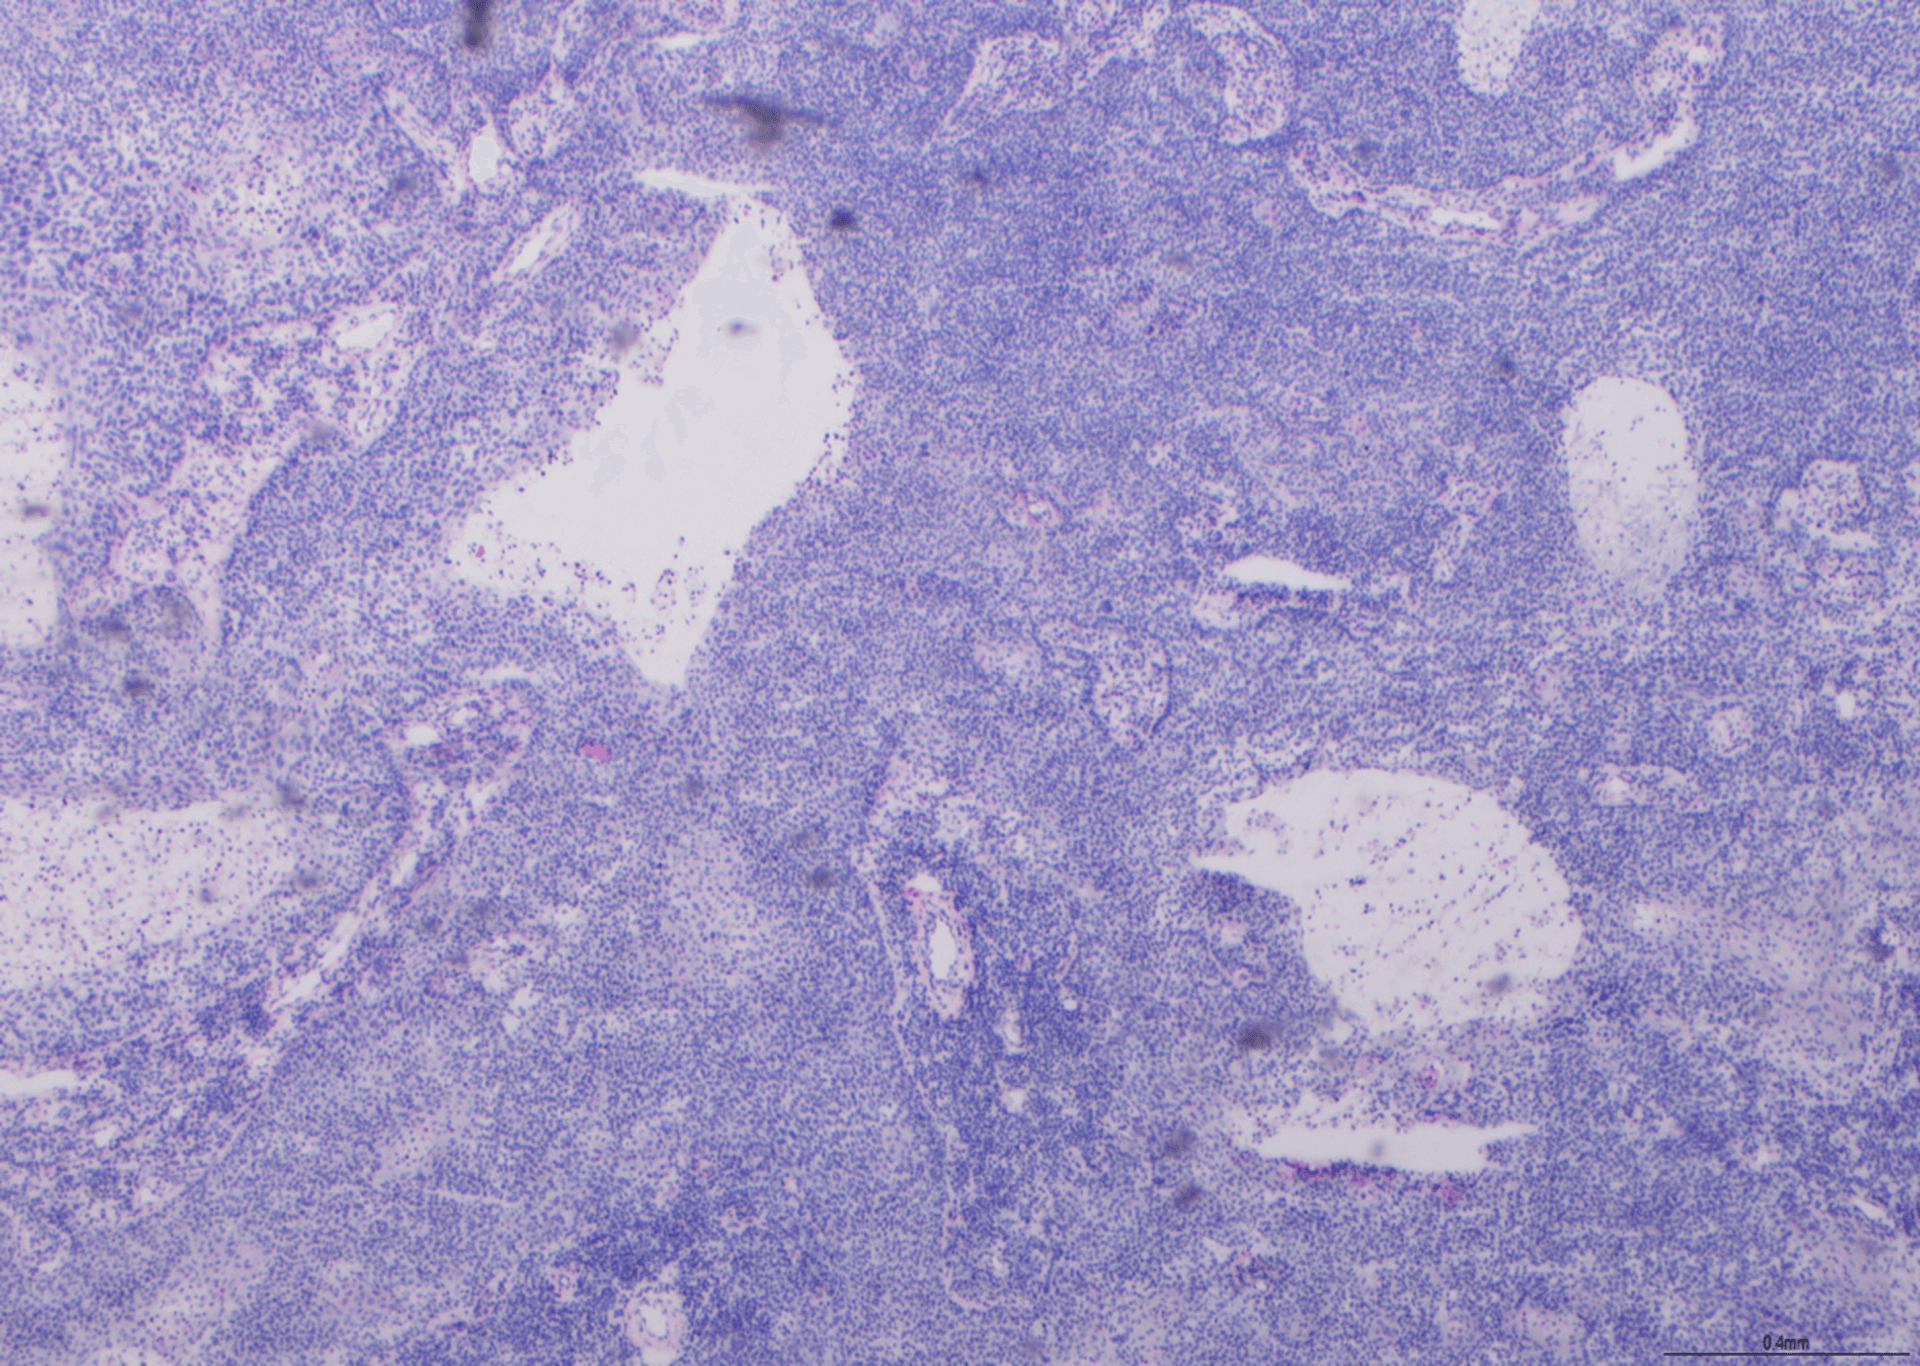

Metenamina Argento - Schema Renale

Osservato a ingrandimento 10x. Non erano presenti glomeruli, il che rende impossibile la valutazione della colorazione della membrana basale glomerulare. Anche il livello di impregnazione d'argento è stato considerato troppo forte, come si può osservare nei tubuli. Sono stati detratti punti in quanto questa sezione è stata considerata "insufficiente per la valutazione". Questo vetrino ha ottenuto un punteggio di 2/10.